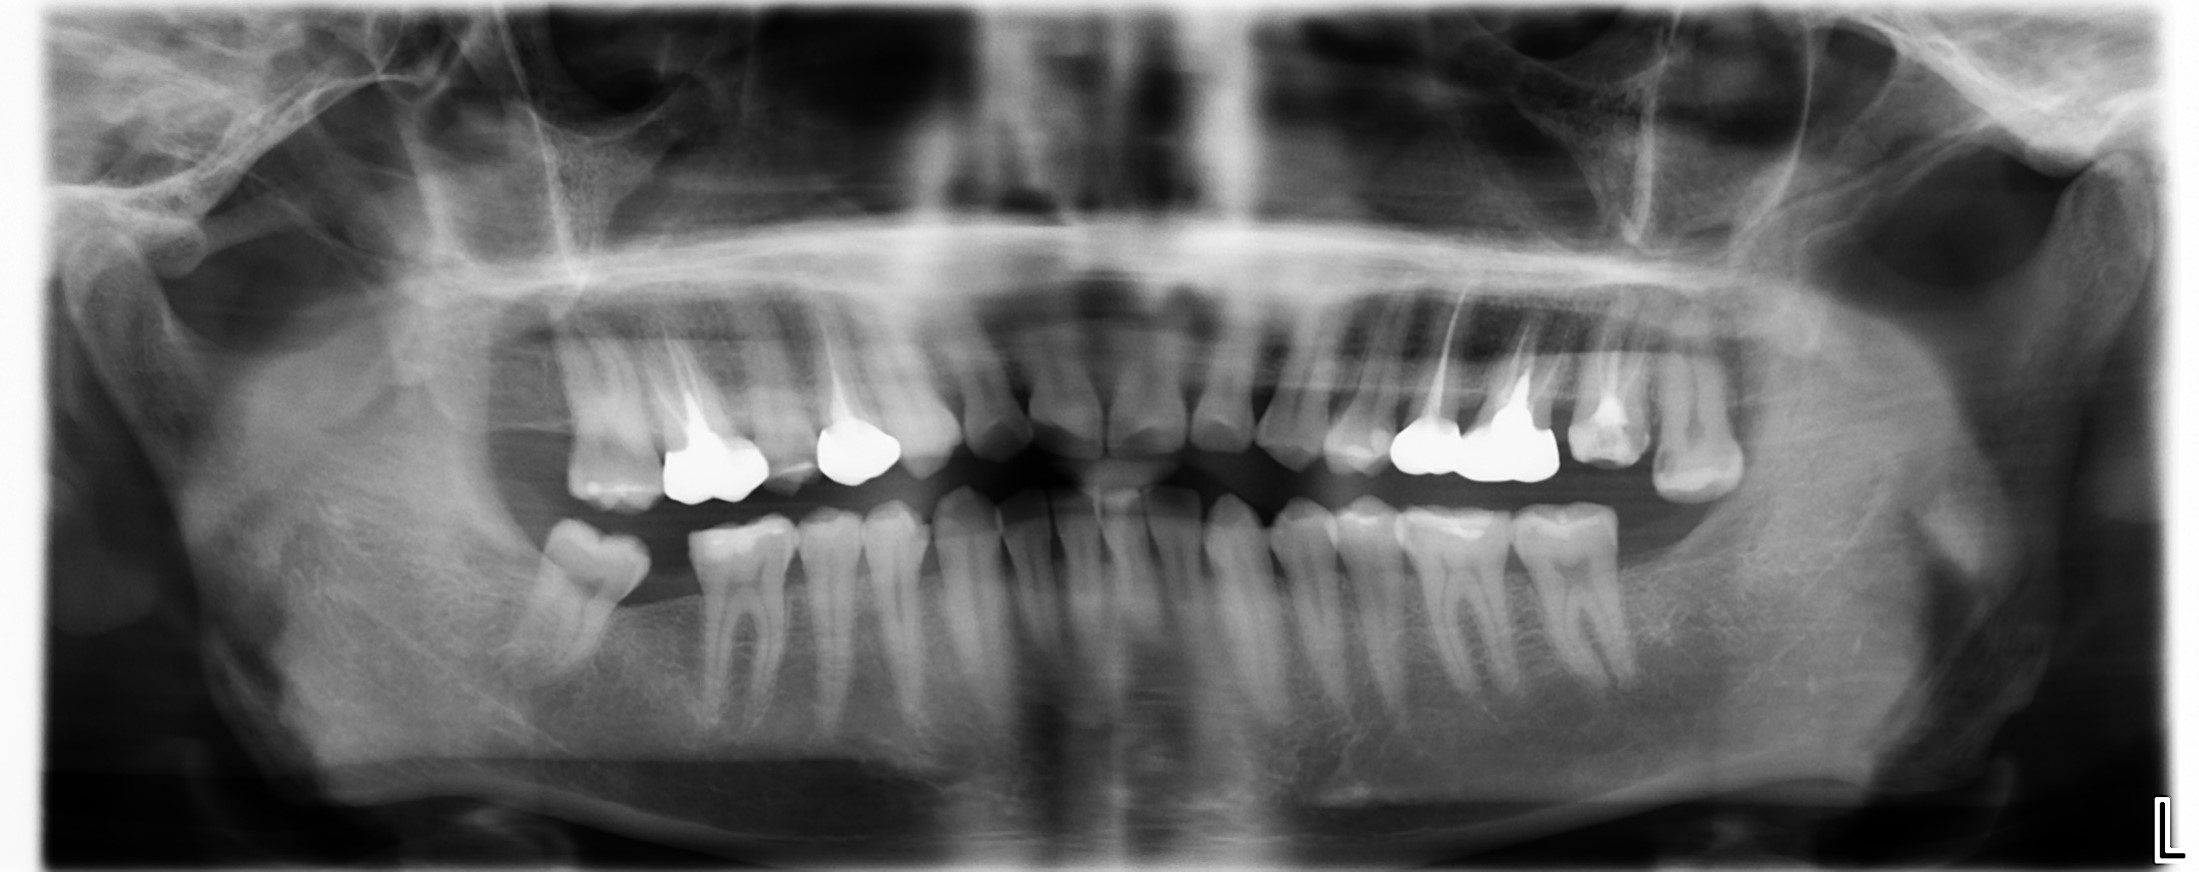

治療前,環口X光,深度蛀牙